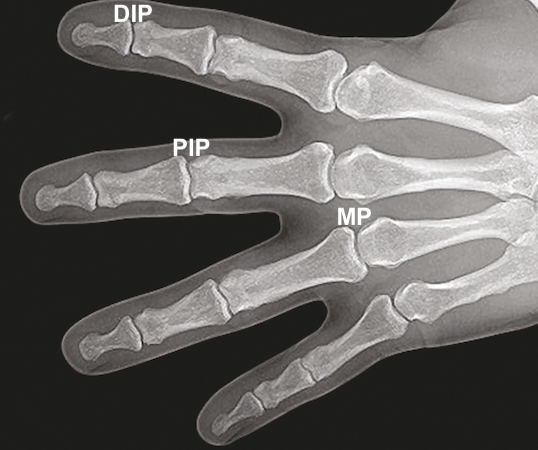

• Hand X-ray showing the DIP, PIP, and MP joints.

Hand X-ray showing the DIP, PIP, and MP joints.